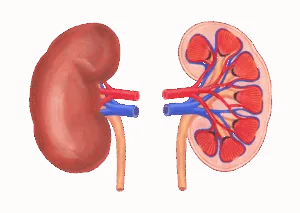

腎臓は、老廃物の排泄や水分・電解質の調整、血圧のコントロール、ホルモンの産生など、身体のバランス維持に欠かせない臓器です。